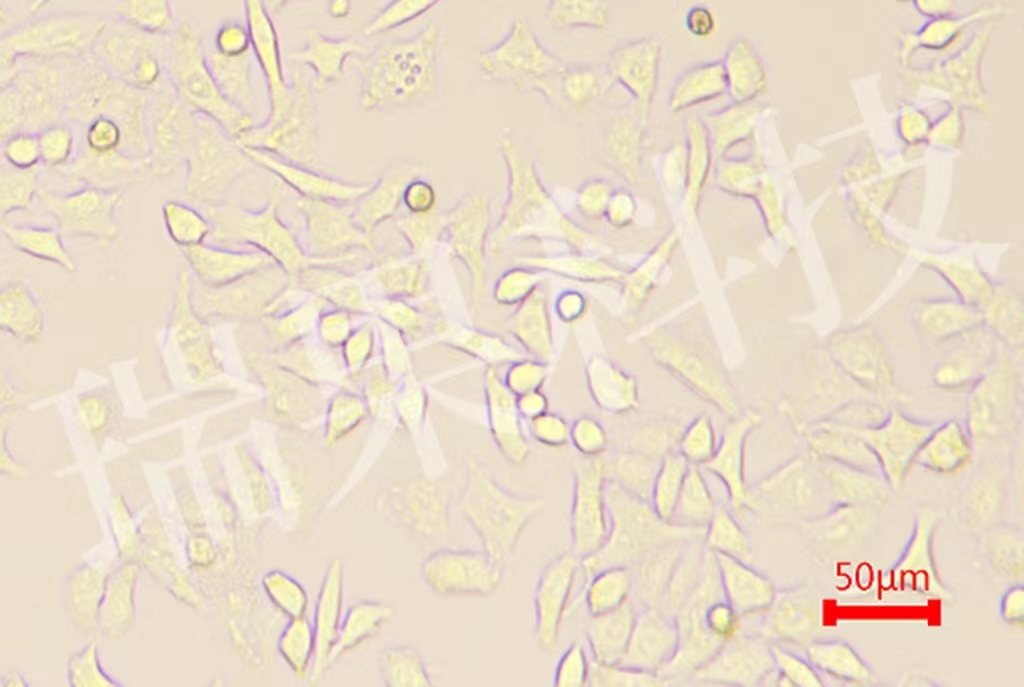

传统的基因测序方法通常基于成千上万个细胞的平均数据,而单细胞测序则能够精确到单个细胞,解析其基因表达、基因突变和表观遗传修饰等特性。这项技术的核心在于将单个细胞分离出来,并对其遗传信息进行高通量测序,以获得超高分辨率的细胞数据。这样一来,科学家便能够揭示细胞之间的异质性,发现那些在传统群体测序中可能被忽略的重要信息。